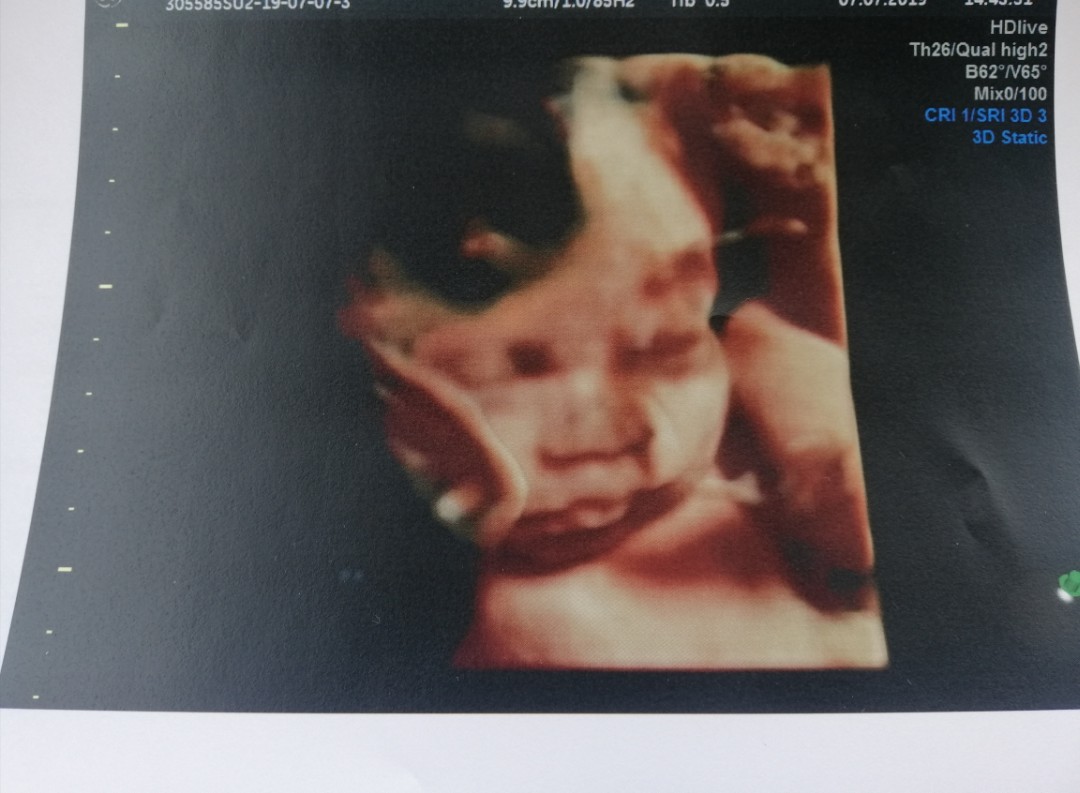

ซาวน์ตอน 28w จ้า